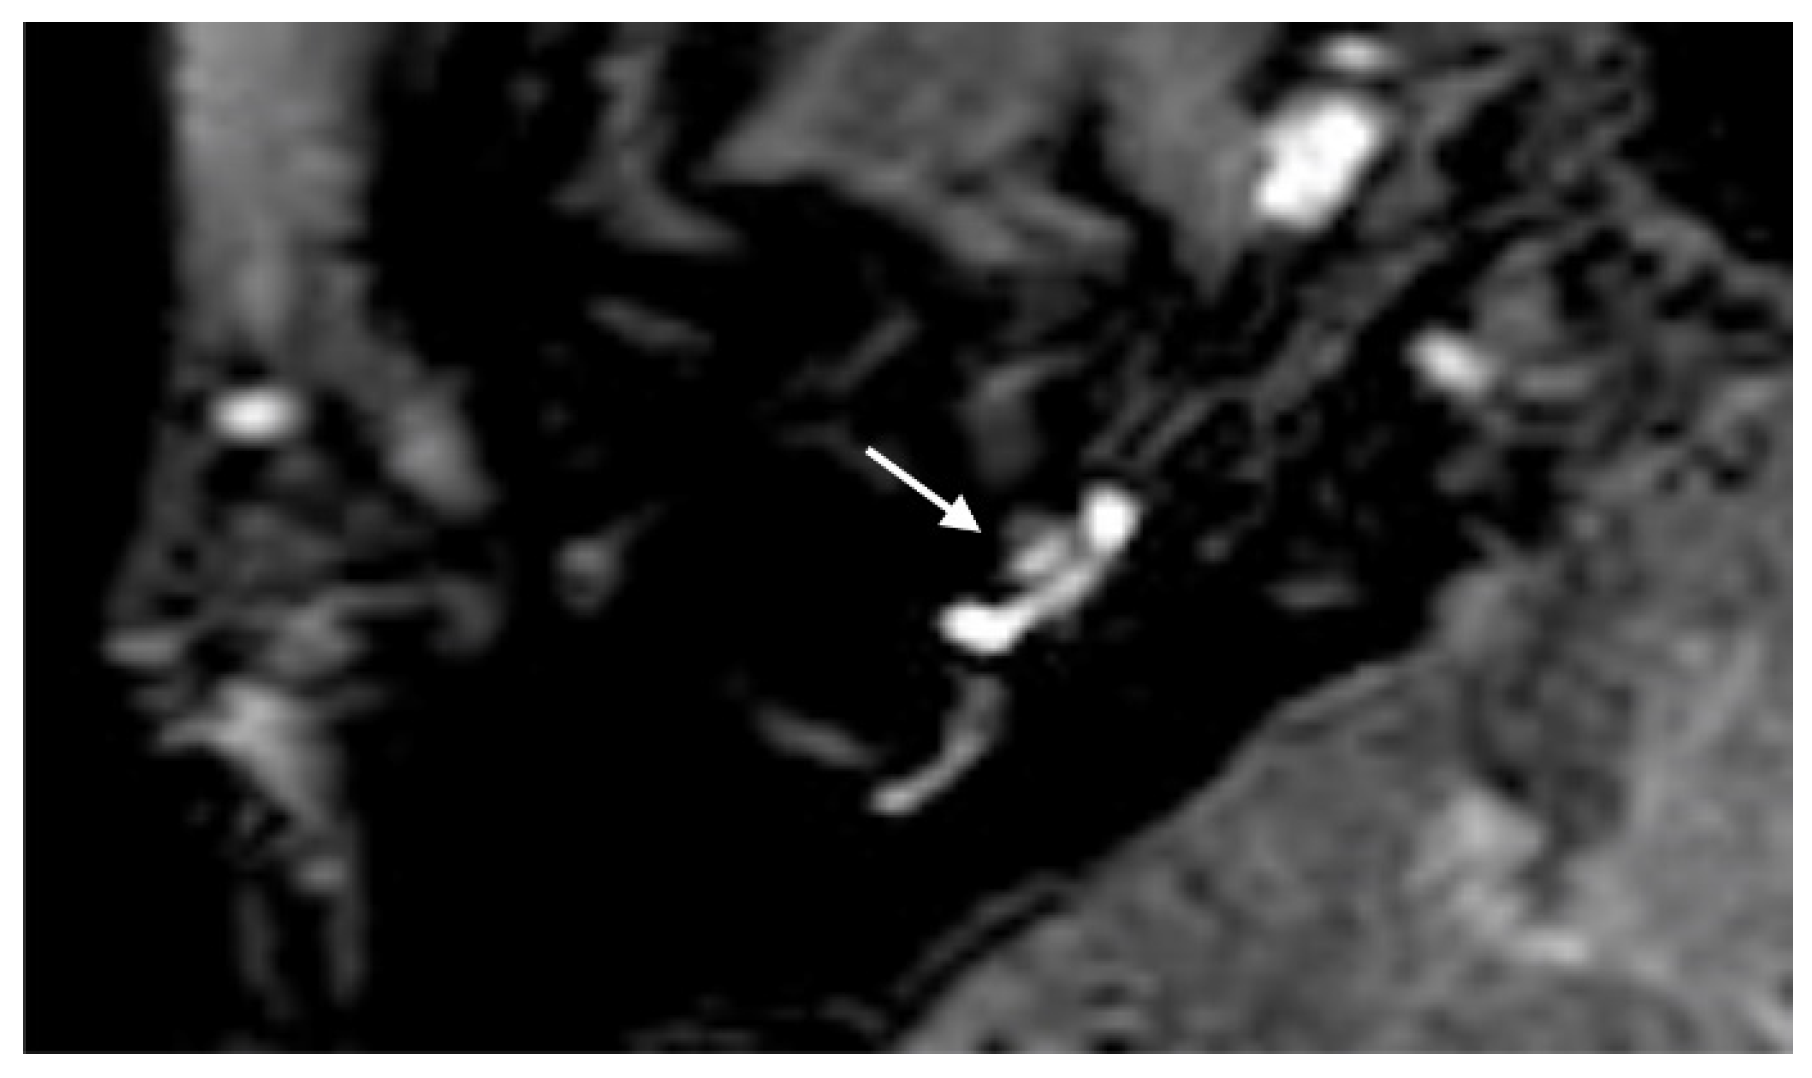

A 48-year-old male presented with a sudden hearing loss on the right side with tinnitus. He showed no vestibular symptoms. The PTA was 110 dB on the right side. Intraoperatively, a PLF track around the RW niche was observed, and the CTP on the right side was positive. A normalized signal intensity of the vestibulum and cochlear was observed on T1W and CE-T1W. A hyperintense signal intensity was found on T2-weighted MRI sequences. On the 4 h delayed 3D-FLAIR image, a contrast enhancement was found in the cochlea, vestibulum, and fundus on the right side of the ear with hearing loss (Figure 3A,B). An RWS was not detected in the affected ear. In this MR sequence, we could also observe a SURI on the right side (vestibular endolymphatic hydrops, grade I) (Figure 3C).

Figure 3. A 48-year-old male presented with a sudden hearing loss on the right side with tinnitus. The axial 4 h delayed 3D FLAIR sequence shows a contrast enhancement in the cochlea basal turn on the right side (A). In the same MR sequence, a vestibulum (arrow (B)) and fundus (dashed arrow (B)) and MR enhancement were observed, as well as an inversion of the saccule (arrow (C)) and utricle (dashed arrow (C)) area ratio.